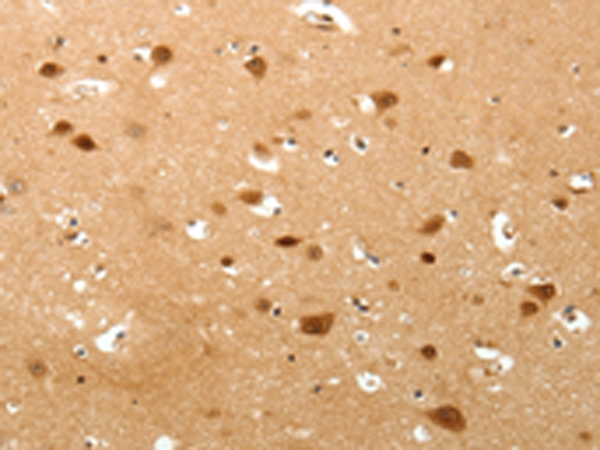

ELISA, IHC |

IHC positive control: |

Human brain and Human lung cancer |

IHC Recommend dilution: |

50-200 |